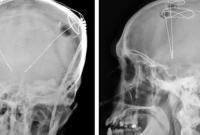

В мозг человеку впервые вставили импланты для борьбы с наркотической зависимостью Здоровье

В больнице Университета Западной Виргинии провели первую в мире операцию, во время которой в мозг пациента вставили импланты, что должно помочь бороться с наркотической зависимостью. В очереди на операцию еще трое пациентов